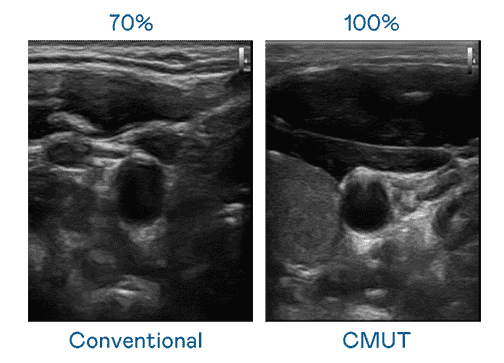

CMUT 技术是一种用电容式微机电元件来产生超音波讯号的技术。。。与传统 PZT 压电式技术相比,,CMUT 频宽增加 30%,,更宽频的超音波讯号让影像解析度大幅提升,,是实现高影像品质医疗超音波扫描、、、、促进精准医疗发展的关键技术。。。

超音波影像的解析度高低,,,首先取决于探头能发出的讯号频宽。。。。JDB电子 CMUT 可提供高清晰的超音波讯号,,,提供高频宽、、、、高灵敏度、、影像纹理细节更高的超音波影像,,,,协助医护人员缩短影像判读时间及利用精准的医疗影像进行诊断。。。